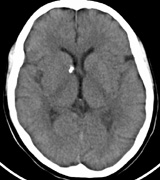

Mental retardation and seizures in TSC are often associated with benign CNS astrocytic hamartomas.131 On imaging, the cerebral lesions show three patterns:132

1. Superficial cortical sclerosis (parenchymal hamartoma) which distort the gyri. Microscopy shows large atypical fibrillary type astrocytes with few associated neurons and areas of calcification.133 The numerous abnormal glial processes and fibers make the tissue abnormally firm or “sclerotic” on palpation (Fig. 13).132

2. Subependymal nodules (SEN) are typically found along the lateral borders of the ventricles and parehncymal brain lesion (“cortical tubers”) (Figs. 14 and 15). Calcification in the first year of life is rare.132

On MRI imaging, the subependymal nodules and parenchymal brain lesions of infants (age ≤3 months) and adults show different signal characteristics. Infant CNS tubers are hyperintense on T1-weighted images and hypointense on T2-weighted images, which is the opposite of the pattern seen in adults.134 Malignant transformation of SEN occurs in about 10% to 15% of patients and the resultant subependymal giant cell astrocytoma accounts for 25% of premature deaths in TSC.135,136

Fig. 14. Tuberous Sclerosis Complex: Sub-Ependymal nodules. These are typically found along the lateral borders of the ventricles.132

Fig. 15. Tuberous Sclerosis Complex. (a) Patient 1: Axial CT scans demonstrating typical calcification of subependymal nodules in a 13-year-old girl with a history of seizures. (b and c) Patient 2. (b) Axial T2-weighted images demonstrate calcified subependymal nodules (arrowheads) and cortical tubers typical of tuberous sclerosis. (c) Widespread cortical tubers are seen on a coronal FLAIR sequence as thickening of the cortex and high signal of the subcortical white matter.